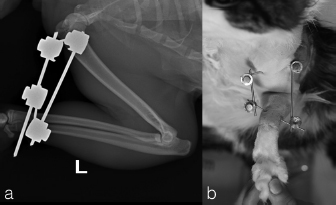

The case 1 and case 2 were evaluated every 5 days until the final evaluation at 22 and 18 days after surgery, respectively. The implants were well tolerated with acceptable three legs gait in both cats. The owners reported no management’s concern of the patient at home. At the final control, the stabilization bars were removed after clinical and radiographic evidence of joint reduction and stability. The Kirschner wires were left for further 5 days later, to be useful in case of reluxation. Protective caps and bandage were applied on the tips of Kirschner wires until their removal. Dermatitis around the pin tracts was the only minor complications associated with the transarticular external skeletal fixation, resolved after implants removal. Thirty days after surgery, in both cases, the clinical examination showed a grade 3/4° lameness (Brunnenberg, 2001), a limited range of motion (150°/70°) and a painless manipulation with no swelling visible. Mild osteoarthrosis was present at radiographic control. For both cats, physiotherapy sessions was not require; however, the owners did some home exercises like gentle passive motions, while restricted movement was continued for another 3 weeks. At 8 weeks after reduction, the cats were no longer lame and the exercise was well tolerated. The range of motion was mildly reduced without pain or joint crepitation. The radiographic follow-up at 2 months after reduction showed mild evidence of osteoarthritis (Fig. 3). The long term follow-up at 3 years assessed with a clinical examination, in both patients, showed normal function and good quality of life despite the mild reduction of the range of motion and moderate development of elbow osteoarthrisis (Fig. 4).

Fig. 3. The radiographic follow-up at two months after reduction showed mild radiographic evidence of osteoarthritis. In the cranio-caudal view (b), near the lateral epicondyle, we can notice a small chip fragment (case 1).

Fig. 4. Long-term radiographic follow-up at three years after surgery showed moderate radiographic evidence of osteoarthritis. Cranio-caudal and medio-lateral views (a-case 1 and b-case 2).